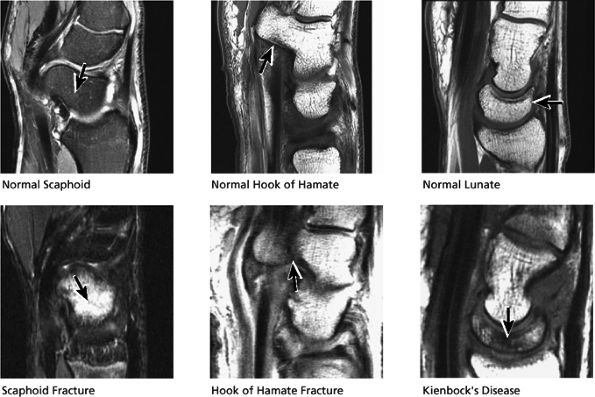

FIGURE 10.33 ● Normal sagittal anatomy. (A) The first carpometacarpal joint, visualized at the top of the field of view on sagittal images, is a common location for degenerative arthrosis. (B) Similar to the hamate, the trapezium also has a “hook,” although it is smaller and is rarely fractured. (C) An anteriorly tipped (or “flexed”) scaphoid is a sign of carpal instability, often associated with scapholunate ligament tears or scaphoid fractures. (D) DISI is suggested when the capitate lunate angle exceeds 30°. When DISI is present, the scapholunate ligament is evaluated for associated tears. (E) Sagittal images afford another opportunity to examine the hook of the hamate for fractures. (F) Triquetral fractures usually occur when the dorsal aspect of the triquetrum is avulsed by the radiotriquetral ligament. Similar to the lateral view on plain films, sagittal images demonstrate the dorsal triquetral avulsion fracture fragment. (G) Sagittal images through the abductor pollicis longus and extensor pollicis brevis tendon afford additional opportunities to identify and characterize the findings of de Quervain's stenosing tenosynovitis. (H) Occasionally, focal prominence of tortuous veins and arteries about the wrist can mimic ganglion cysts on sagittal fluid-sensitive sequences. These vessels can be distinguished from ganglions by viewing successive images and visualizing continuity of the vascular structures. (I) Tears and sprains of the dorsal and volar extrinsic capsular ligaments are optimally visualized in the sagittal plane. (J) The longitudinal extent and length of median nerve involvement in median neuritis can be measured and characterized in the sagittal plane. (K) Near its radial attachment, the triangular fibrocartilage fans out to a broad, bowtie-shaped structure, resembling the appearance of the meniscus on sagittal images of the knee. (L) Near its ulnar attachment, the triangular fibrocartilage is visualized as a short, narrow band of hypointense cartilage that represents the convergence of the dorsal and volar radial ulnar ligaments at the apex of the triangular TFC.

Fractures of the carpal bones, including the hook of the hamate, scaphoid, and lunate